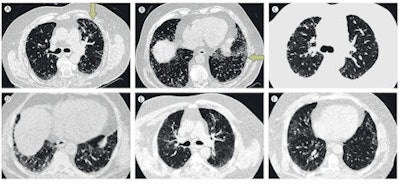

High-resolution axial CT images of upper and lower lung. A-B: Usual interstitial pneumonia; images show peripheral predominant, basal predominant reticular abnormality with mild subpleural honeycombing (B, arrows). The extent of honeycombing is < 5%. C-D: Possible usual interstitial pneumonia; images show peripheral predominant, basal predominant reticular abnormality without honeycombing. E-F: Inconsistent pattern of usual interstitial pneumonia; images show upper lung predominant abnormality characterized by ground glass abnormality with mild reticular abnormality. Images courtesy of Dr. Ganesh Raghu, reproduced with permission from the Lancet Respiratory Medicine.